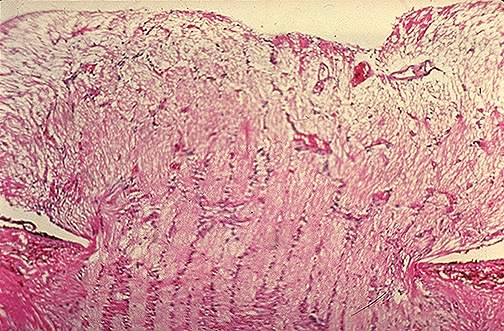

| This microscopic section through the head of the optic nerve displays papilledema. Note the bulging of the nerve above the level of the surrounding retina with forward bowing of the lamina cribrosa. The intracranial pressure must be relieved, or the patient may suffer herniation (cerebellar tonsils, uncus of hippocampus, cingulate gyrus). [Image contributed by Nick Mamalis, MD, University of Utah] |